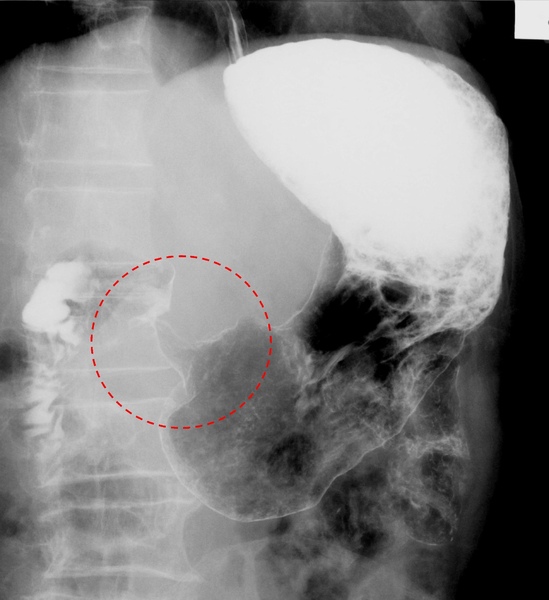

下面這一張是上消化到攝影中,胃癌的模樣,胃黏膜的紋路糾結在一塊兒。

這一張上消化到攝影裡,可以見到胃癌使的胃末端縮成了漏斗狀。

像這般胃癌堵在胃通往十二指腸的道上,患者會出現持續嘔吐的症狀。

當胃出口被塞住後,整個胃便會像灌氣球一般大大鼓起。一段時間後,撐飽飽的胃也就成了肚子裡最大的器官了。